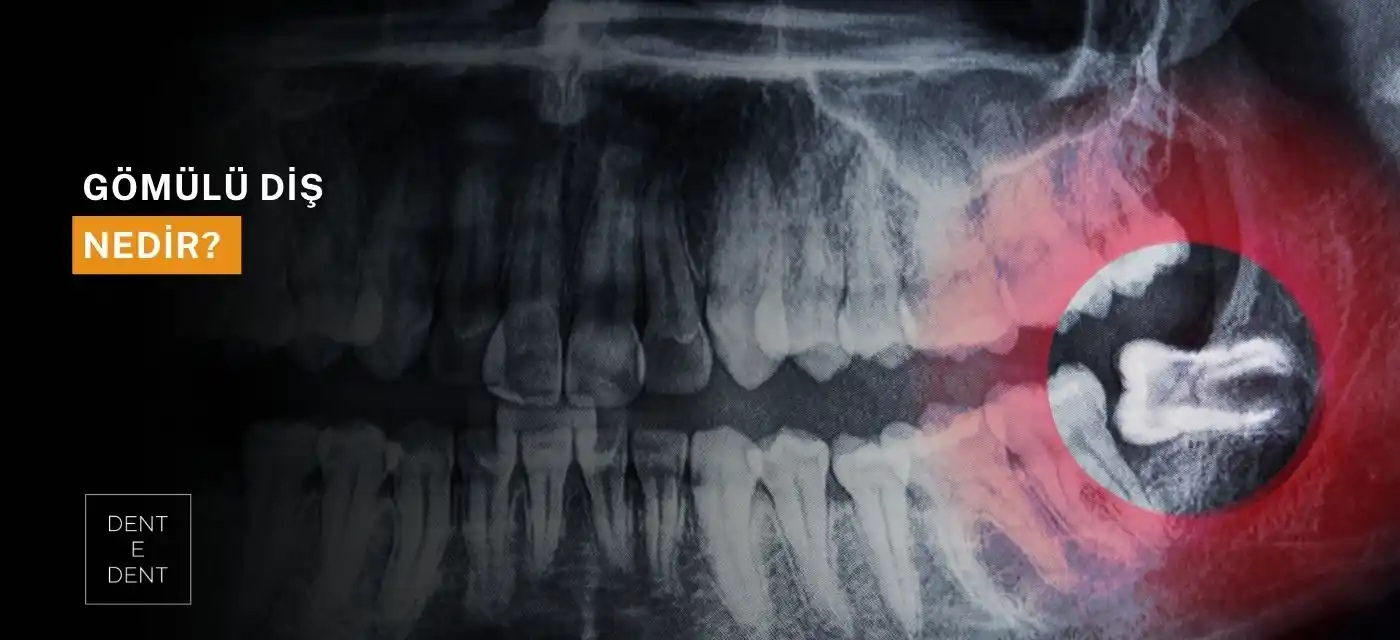

Gömülü Diş Nedir?

Sürmesi tamamlanamayan dişler, ağız içinde doğru konumuna ulaşamayan ve normal gelişim sürecini tamamlayamayan yapılar olarak tanımlanır. Bu durum genellikle üçüncü azı dişlerinde yani yirmilik dişlerde gözlenir.

Çene yapısı, diş sıralaması veya yetersiz alan gibi etkenler, bu dişlerin sağlıklı biçimde yüzeye çıkmasını engeller. Rutin diş hekimi kontrolleri, sorunun erken fark edilmesini ve uygun müdahalenin planlanmasını sağlar.

Bazı durumda dişler, çevredeki dokulara baskı yaparak ağrı, hassasiyet veya enfeksiyon gibi rahatsızlıklara yol açabilir. Panoramik röntgen ve muayene, ayrıntılı değerlendirme yapılmasına yardımcı olur. Alt ve üst bölgedeki yirmilik dişlerin yönelimi ve konumu da cerrahi planlamada belirleyici rol oynar.